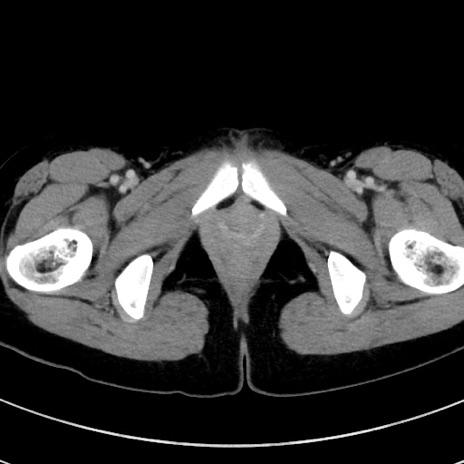

症例17(横断像)

【症例】20歳代女性

【主訴】嘔吐、下腹部痛

【現病歴】昨日夕食後に嘔吐し下腹部痛が出現。本日になっても嘔吐持続し改善しないため来院。

【身体所見】意識清明、BT 37.2℃、BP 108/67mmHg、腹部:平坦、やや硬、下腹部正中から右にかけて圧痛あり、反跳痛軽度あり、tapping pain(+)。

【データ】WBC 13600、CRP 14.94